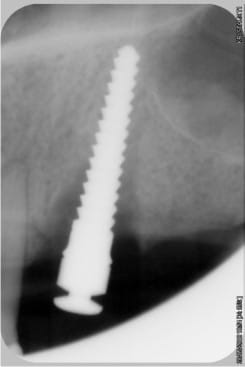

les contrôles radios

--

xbk